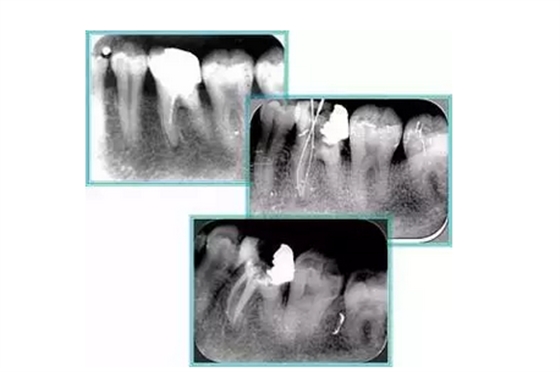

左圖和上圖為干髓治療后牙齒,齲齒疏通后進(jìn)行根管充填。

如圖為塑化加根充處理后牙齒 X 線片。

6. 鈣化

常見有修復(fù)性鈣化和增齡性鈣化。下面為根管鈣化 X 線片。

右圖及下圖為器械折斷的 X 線片。箭頭處示折斷器械。